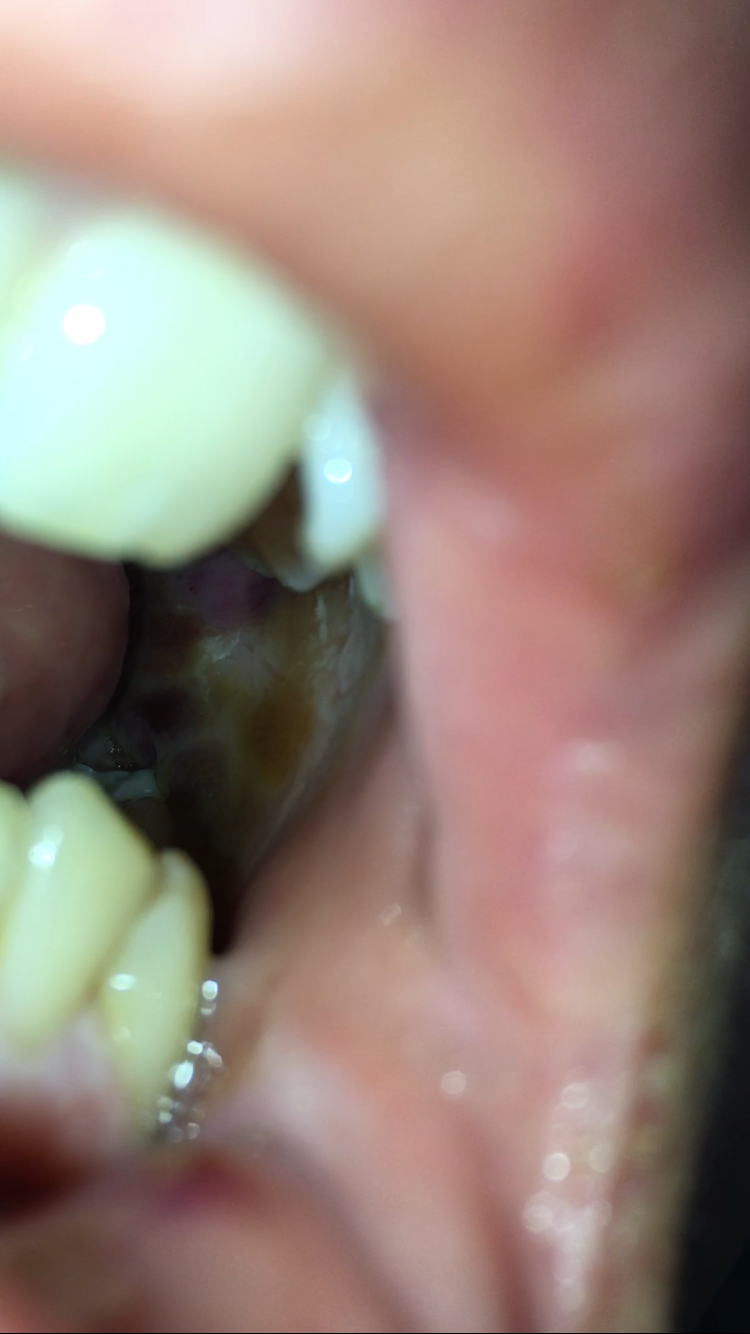

Dort entscheidet der Zahnarzt auch ob die Fäden gezogen werden können. Da eine Weisheitszahnwunde aufgrund der OP auch nach 3 Monaten noch nicht völlig verschlossen ist haben sich dort Speisereste festgesetzt wodurch Du jetzt eine Entzündung hast. Nach etwa zwei Wochen waren die Wunden komplett verheilt die Schwellung war weg und auch die Blutergüsse sind verschwunden.

Jetzt hat eine Seite seit gestern wieder eine leichte Schwellung. Das Kauen würde eine zu hohe Belastung für dich darstellen und die Wunde könnte aufgehen. Nicht annähernd so stark wie nach der op aber dennoch sichtbar.

Der erste Tage nach der Weisheitszahn OP. Nicht annähernd so stark wie nach der op aber dennoch sichtbar. Die Wunde wieder zu öffnen und die Wunde zu reinigen. Um den Mund sauber zu halten und Infektionen zu vermeinen können ab dem zweiten Tag die Zähne sanft geputzt werden. Bei den meisten Menschen zwischen 17 und 24 Jahren kommt es zum Wachstum von Weisheitszähnen. Bis sich die Wunde nach der Weisheitszahn OP geschlossen hat dauert es nur einige Tage. Jetzt habe ich von einigen gehört und im Netz gelesen dass nach dem entfernen der Fäden Löcher bzw. Das Kauen würde eine zu hohe Belastung für dich darstellen und die Wunde könnte aufgehen. Sie werden die Auswirkungen dann als minimal wahrnehmen und die Weisheitszahn-Operation als kleinen Eingriff.